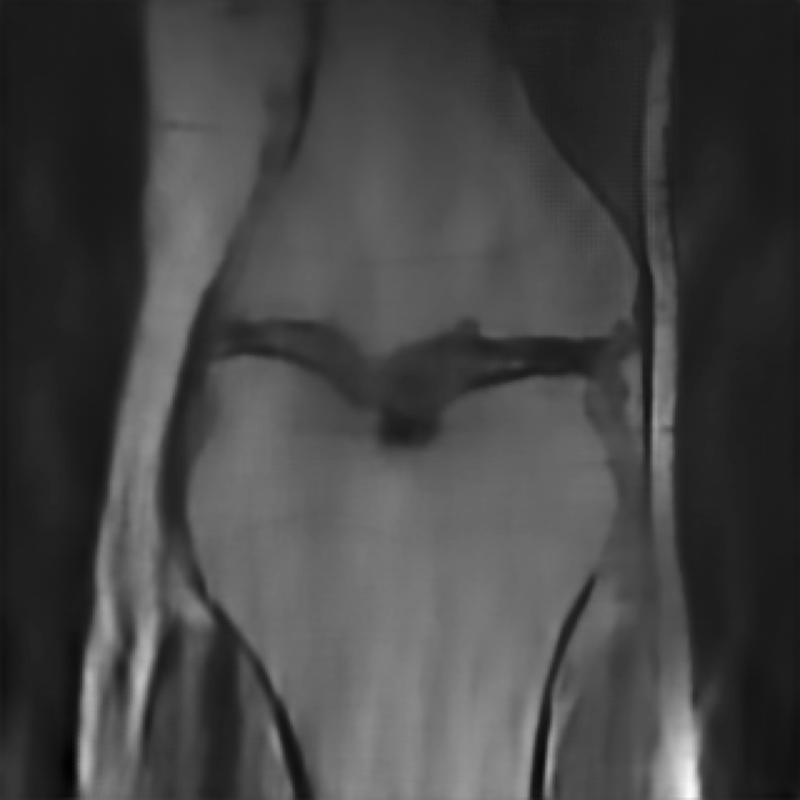

The data used in the undersampled MRI experiments were obtained from the NYU fastMRI Initiative [45]. The primary goal of the fastMRI dataset is to test whether machine learning can aid in the reconstruction of medical images. We trained and tested on a subset of the single-coil knee dataset, which consist of simulated single-coil measurements. In all tests, we use complex-valued data, which interfaces with our deep networks by treating the real and imaginary parts of the images as separate channels. We measure reconstruction accuracy with respect to the center 320320 pixels of the complex IFFT of the fully-sampled k-space data. For the purpose of visualization, we display only the magnitude images in the following sections.

In Table 1 we present our main results. We present sample reconstructions for the deblurring problem and MRI reconstruction problem in Figs. 7 and 8. For reference, the ground truth, inputs to the networks, a total variation regularized reconstruction, and a RED reconstruction are presented in Figs. 5 and 6. We also provide in the Appendix a table of SSIM values as well as the full version of Table 1, which contains the standard deviations of PSNR.

While the magnitude of the improvements vary across domains and problems, we find that retraining the network with the proposed model adaptation techniques significantly improve performance by several dBs in the new setting. This effect is particularly striking in the case of MRI reconstruction with MoDL, where the βnaiveβ approach of replacing with in the network gives catastrophic results (a roughly 9 dB drop in reconstruction PSNR), while the proposed model adaptation approaches give reconstruction PSNRs within 1-2 dB of the baseline approach of training and testing with the same forward model in the case where is known.